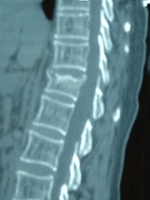

(1)骨影像學檢查和骨密度①攝取病變部位的X線片X線可以發現骨折以及其他病變,如骨關節炎、椎間盤疾病以及脊椎前移。骨質減少(低骨密度)攝片時可見骨透亮度增加,骨小梁減少及其間隙增寬,橫行骨小梁消失,骨結構模糊,但通常需在骨量下降30%以上才能觀察到。大體上可見椎體雙凹變形,椎體前緣塌陷呈楔形變,亦稱壓縮性骨折,常見於第11、12胸椎和第1、2腰椎。②骨密度檢測骨密度檢測是骨折的預測指標。測量何部位的骨密度,可以用來評估總體的骨折發生危險度;測量特定部位的骨密度可以預測局部的骨折發生的危險性。